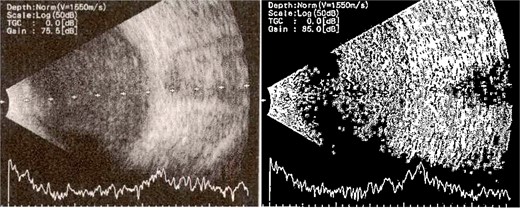

Patient 3: A 63-year-old Saudi female reported pain and decreased vision in her right eye. On examination 4 days post-surgery, her vision was PL. Examination findings included severe conjunctival injection (Fig. 5). B-scan (Fig. 6). Treatment included vitreous tap and intravitreal antibiotics.

B-scan ultrasound demonstrating mild to moderate vitritis in endophthalmitis case for patient 3.